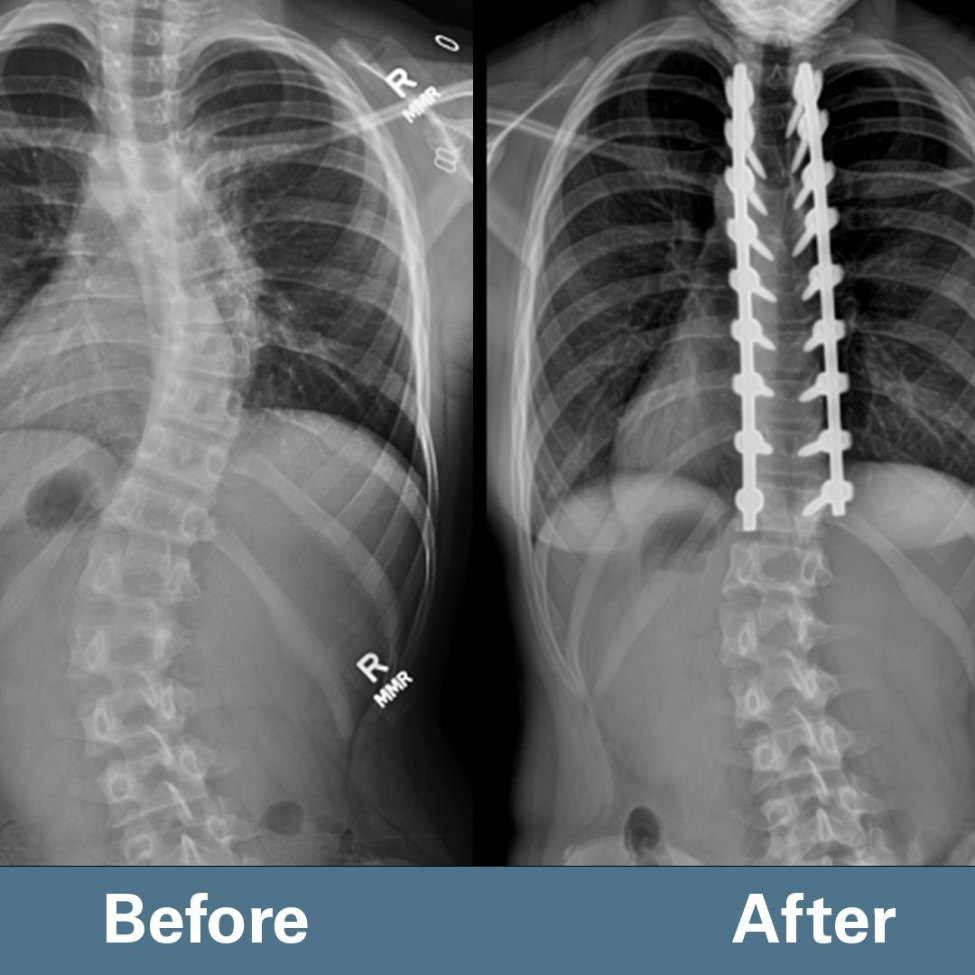

Ellison’s scoliosis curve improved from 48 degrees to less than 10 degrees as a result of bracing and spine surgery.

“By doing this selective thoracic fusion, we’re able to correct the big curve in the thoracic spine, but also improve the lower curve without operating on it,” Borden said. “This allows for continued motion in that area below where we do the surgery to maximize her ability to do the things she enjoys, particularly dance.”

During the four-hour surgery, Borden inserted two rods and 18 screws in order to correct her spinal deformity. Ellison has a 11-inch scar down the middle of her back as a result. “The hope is that this procedure prevents the curves from getting any bigger, provides Ellison with a spine that does not need further surgery, and gives her a full, active, rich life into adulthood,” Borden said.